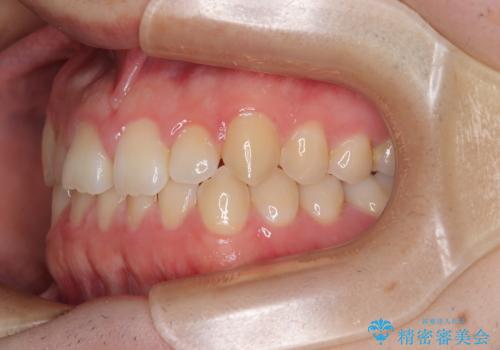

- 「前歯のすきっ歯が気になる」「食べ物が歯の間に詰まりやすい」とのお悩みで来院された20代男性の患者様です。

歯と歯の間に隙間がある**空隙歯列(すきっ歯)**は、見た目の問題だけでなく、食片圧入による歯肉の腫れや、隣接面う蝕のリスク増加につながることがあります。

診査により舌突出癖が認められました。この癖は、すきっ歯の原因となるだけでなく、矯正後の後戻りリスクを高めます。

そこで矯正治療と並行して**MFT(口腔筋機能療法)**を実施し、舌や口周囲筋の正しい使い方を習得していただきました。